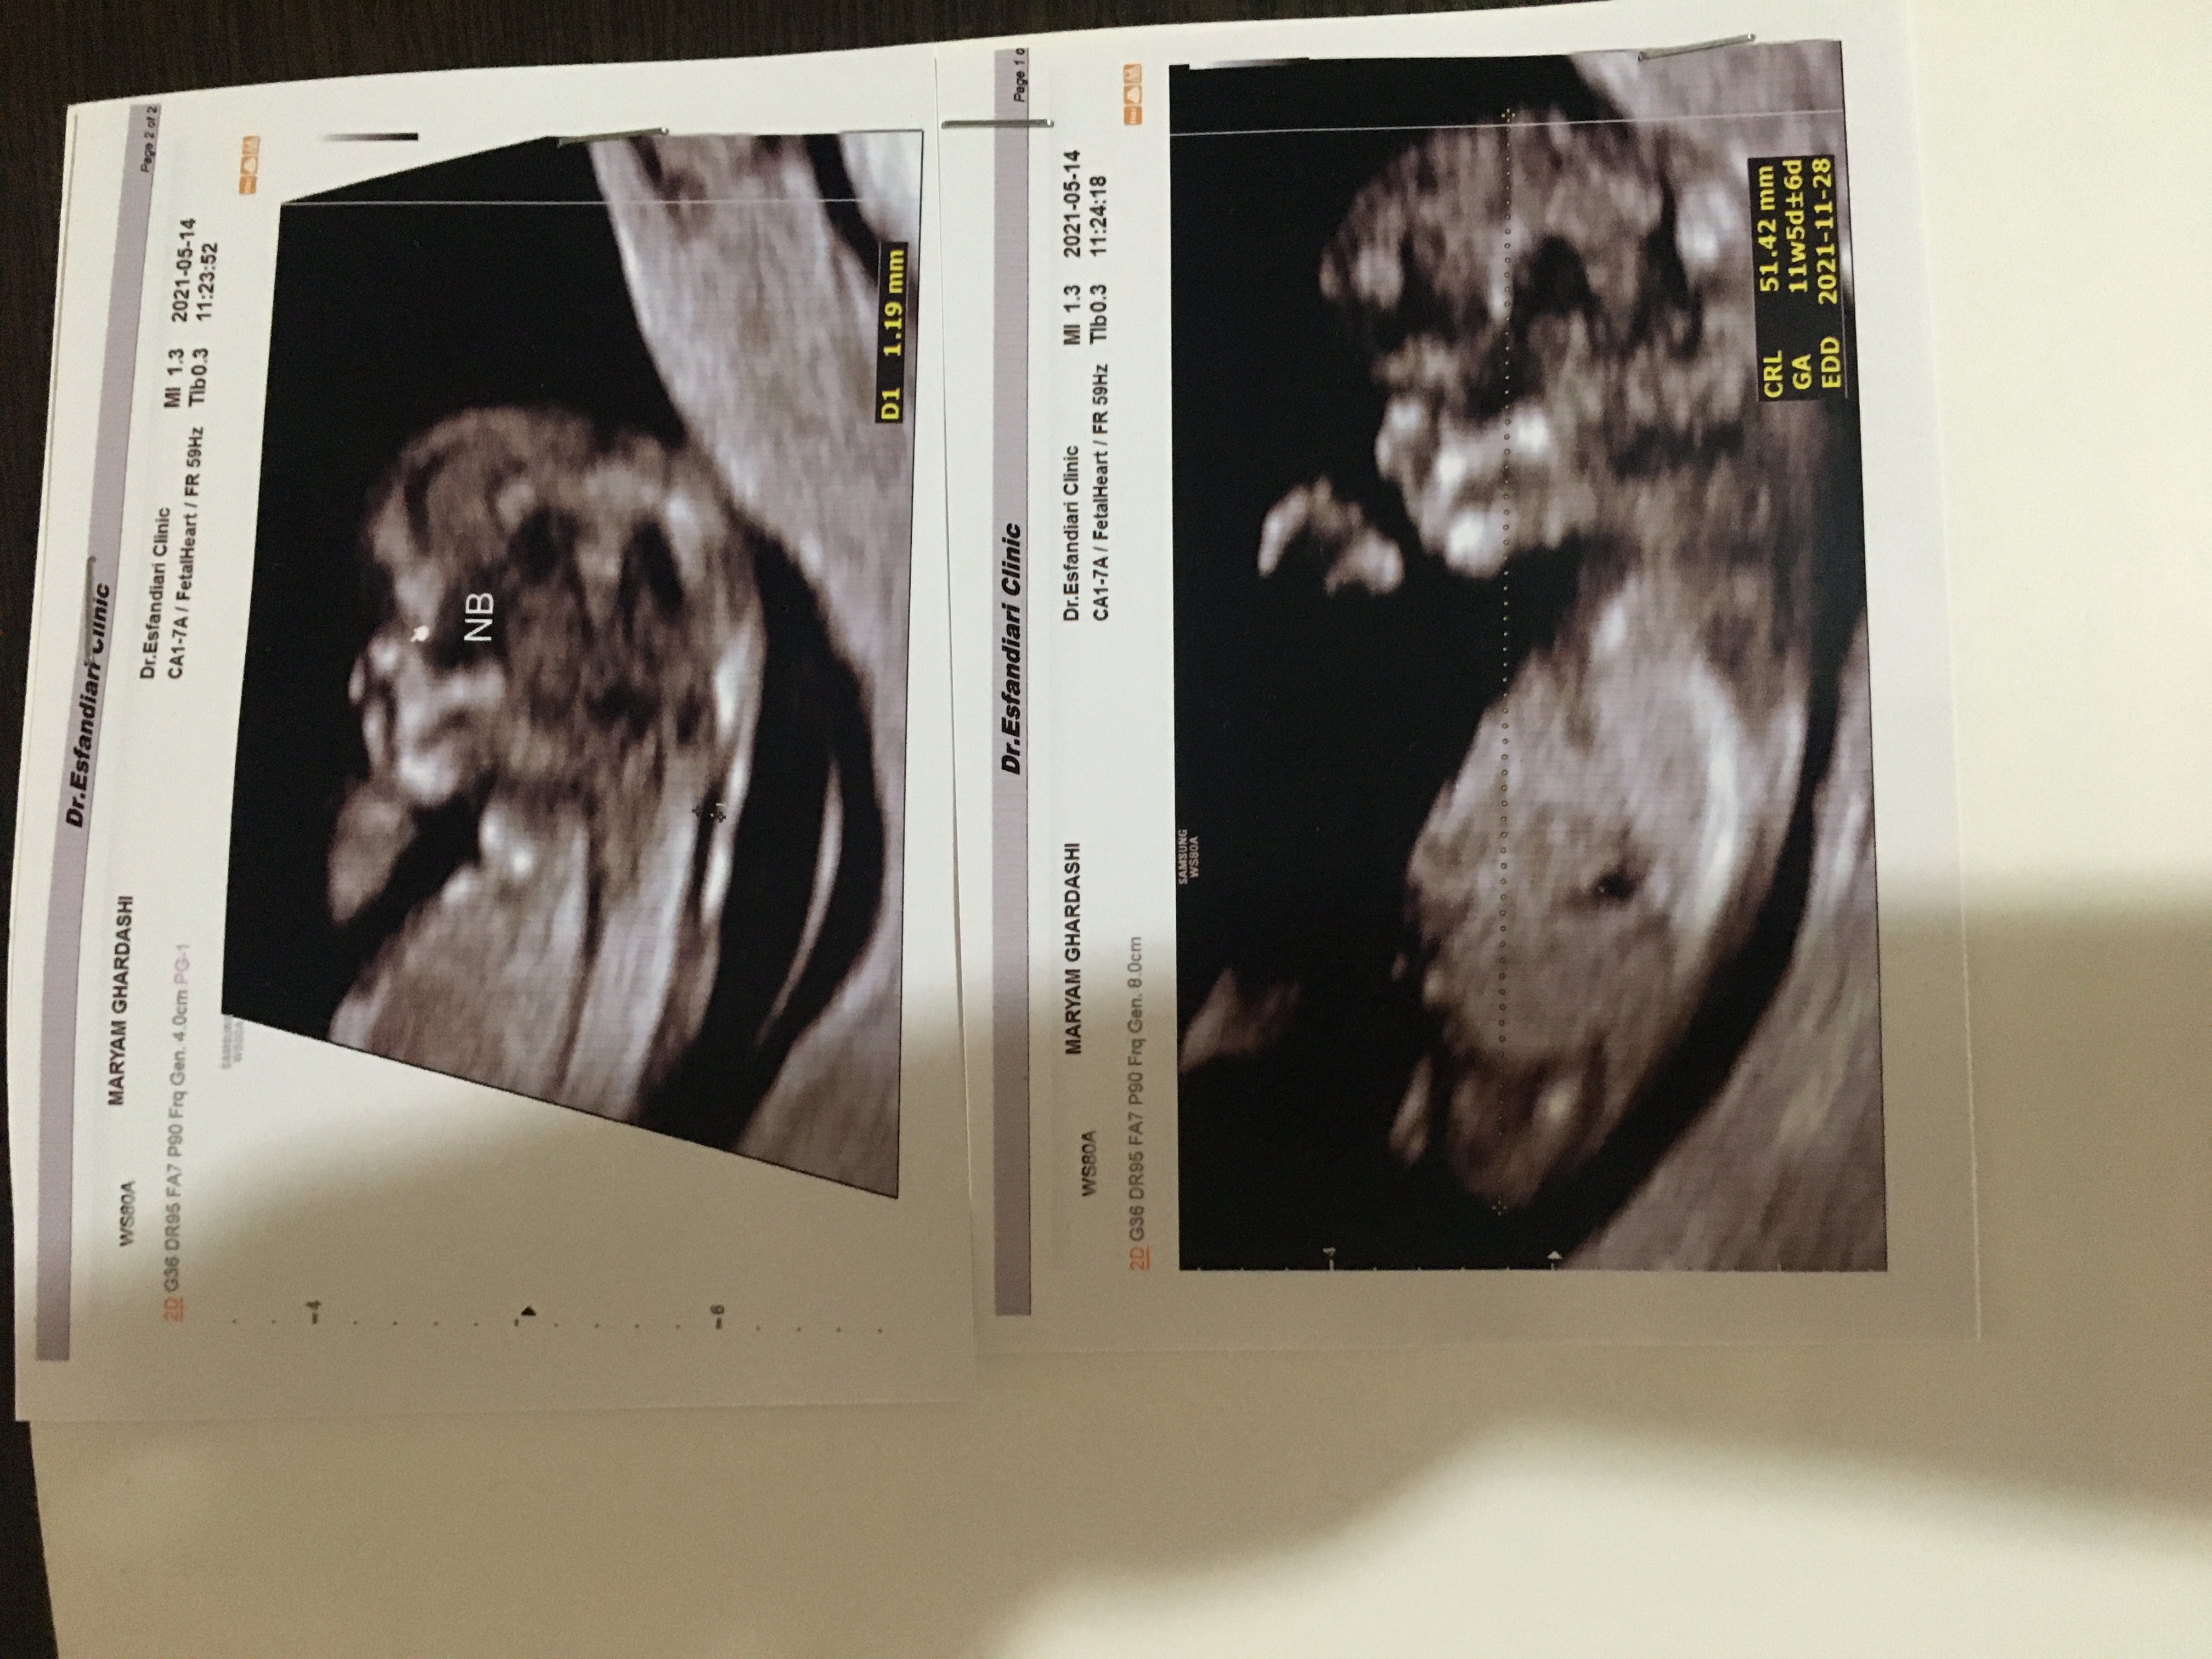

ببین مال من چیه رفتم سونو

برا سلامتی پسرام و نی نی تو دلیم یه صلوات بفرس